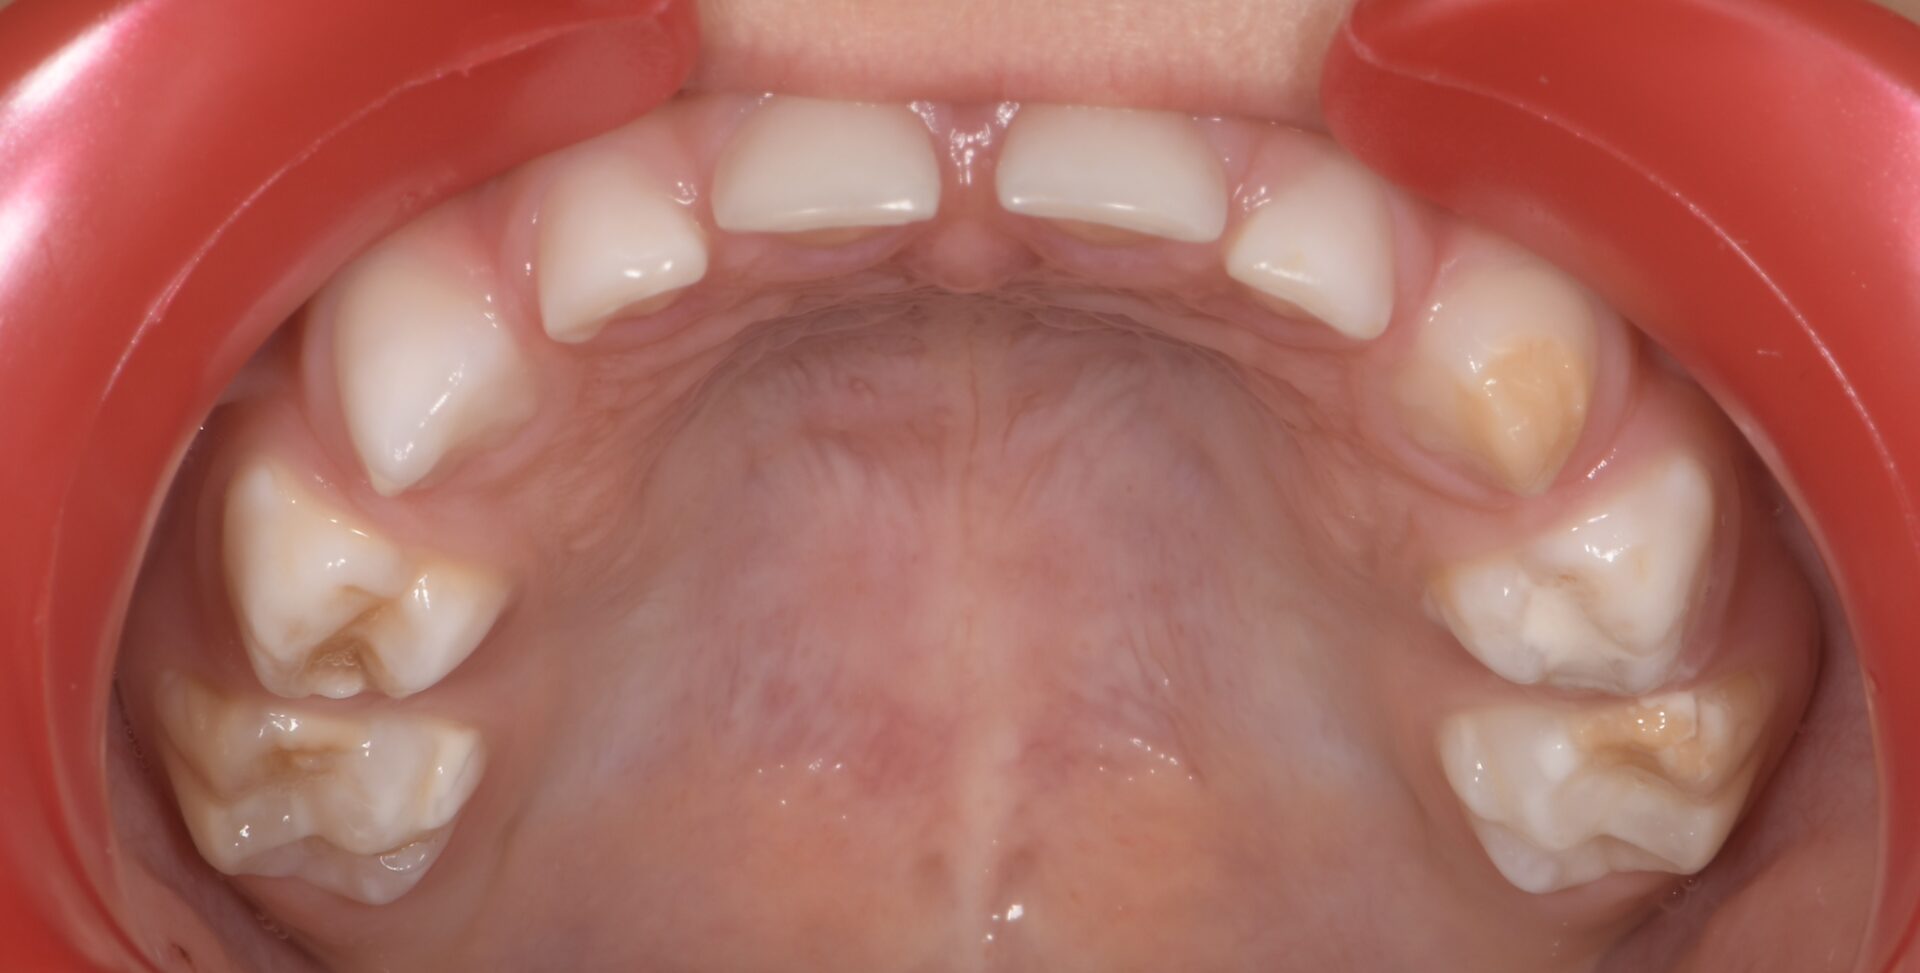

L’équivalent en denture temporaire est appelée HSPM pour Hypomineralised Second

primary Molar (Figures 5-6) (4).

formation dentaire pédodontie Figure 5.

formation dentaire pédodontie Figure 6.

Un enfant présentant une HSPM a 5 fois plus de risques de présenter également une MIH en denture permanente.

Figure 5-6 : Arcades maxillaire et mandibulaire d’un enfant atteint de HSPMfF